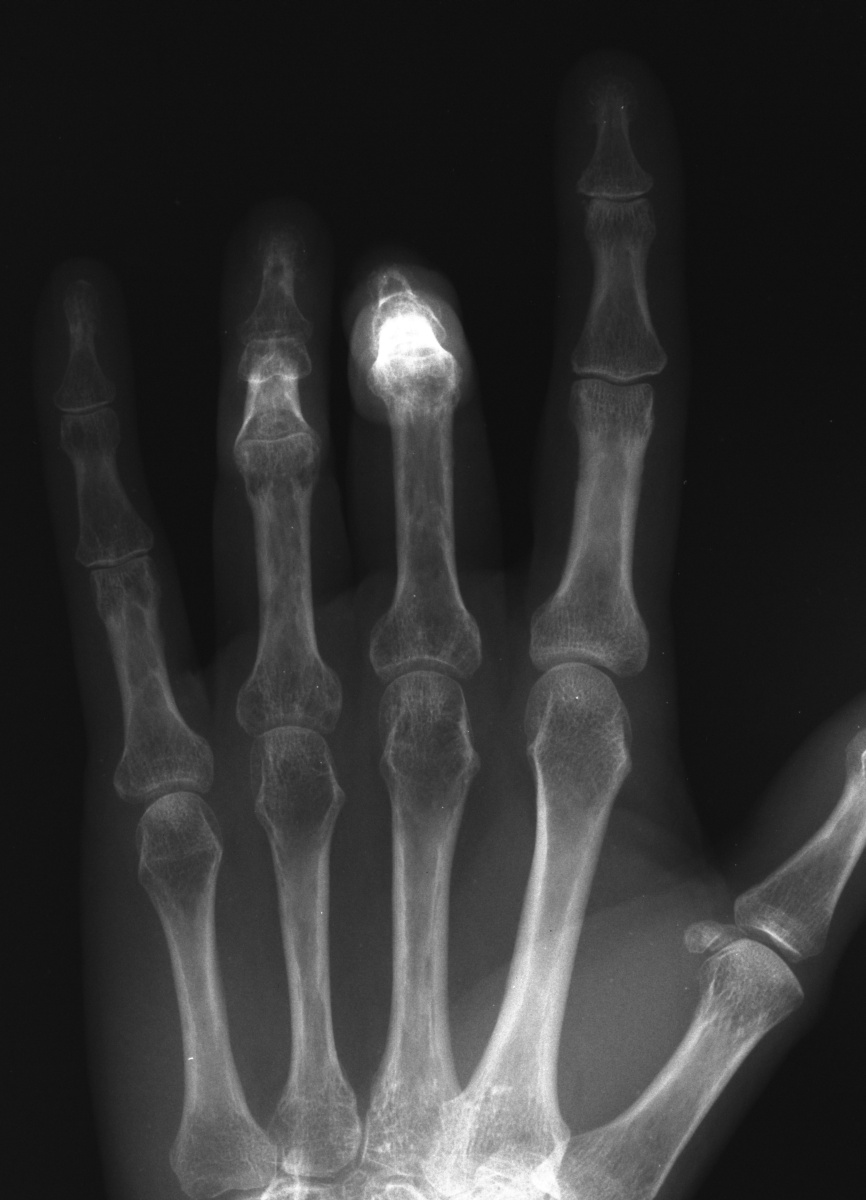

Four years ago, this patient  sustained closed middle finger PIP dislocation a ring finger intraarticular middle phalanx base fracture. She developed painful reflex sympathetic dystrophy. PIP and DIP joint stiffness developed during the painful phase and remained  after resolution of all other RSD related issues.

Range of motion was limited: middle PIP fixed at 90 degrees; ring PIP fixed at 80. The middle DIP is stiff at 0 degrees; the ring DIP ranges only from 0 to 20 degrees hyperextension.

Modified AP views taken with the middle phalanges flat on the radiograph plate show preservation of joint anatomy.